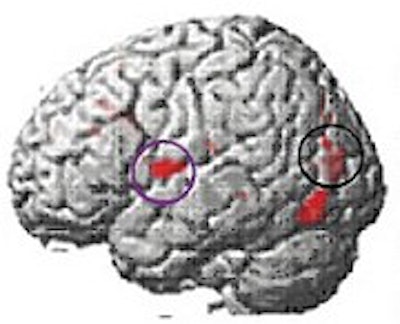

At the beginning of the study, MRI scans of the 20 dyslexic subjects contrasted sharply with those of the 12 normal readers in the control group; the dyslexic subjects' scans showed a lack of activity in the language-critical temporal regions of the brain.

Brain function in child with no reading disability (top); brain function in child with developmental dyslexia (middle); children with dyslexia show increased brain function after training (below). Images courtesy of Elise Temple, Ph.D.

At the end of the eighth week, the investigators found that, among the dyslectic subjects, areas of the brain critical to reading skills had become activated, and had begun to function more normally. Other regions of the brain also showed activity on the MRI scans, suggesting a gradual compensatory process that would help the dyslexic subjects learn to read more fluently.

"This fMRI study demonstrates that a training program explicitly designed to mimic the learning routines used in neuroplasticity studies with animals results in significant amelioration of aberrant metabolic activity in dyslexic subjects in (brain) areas important for phonological processing," Tallal wrote.